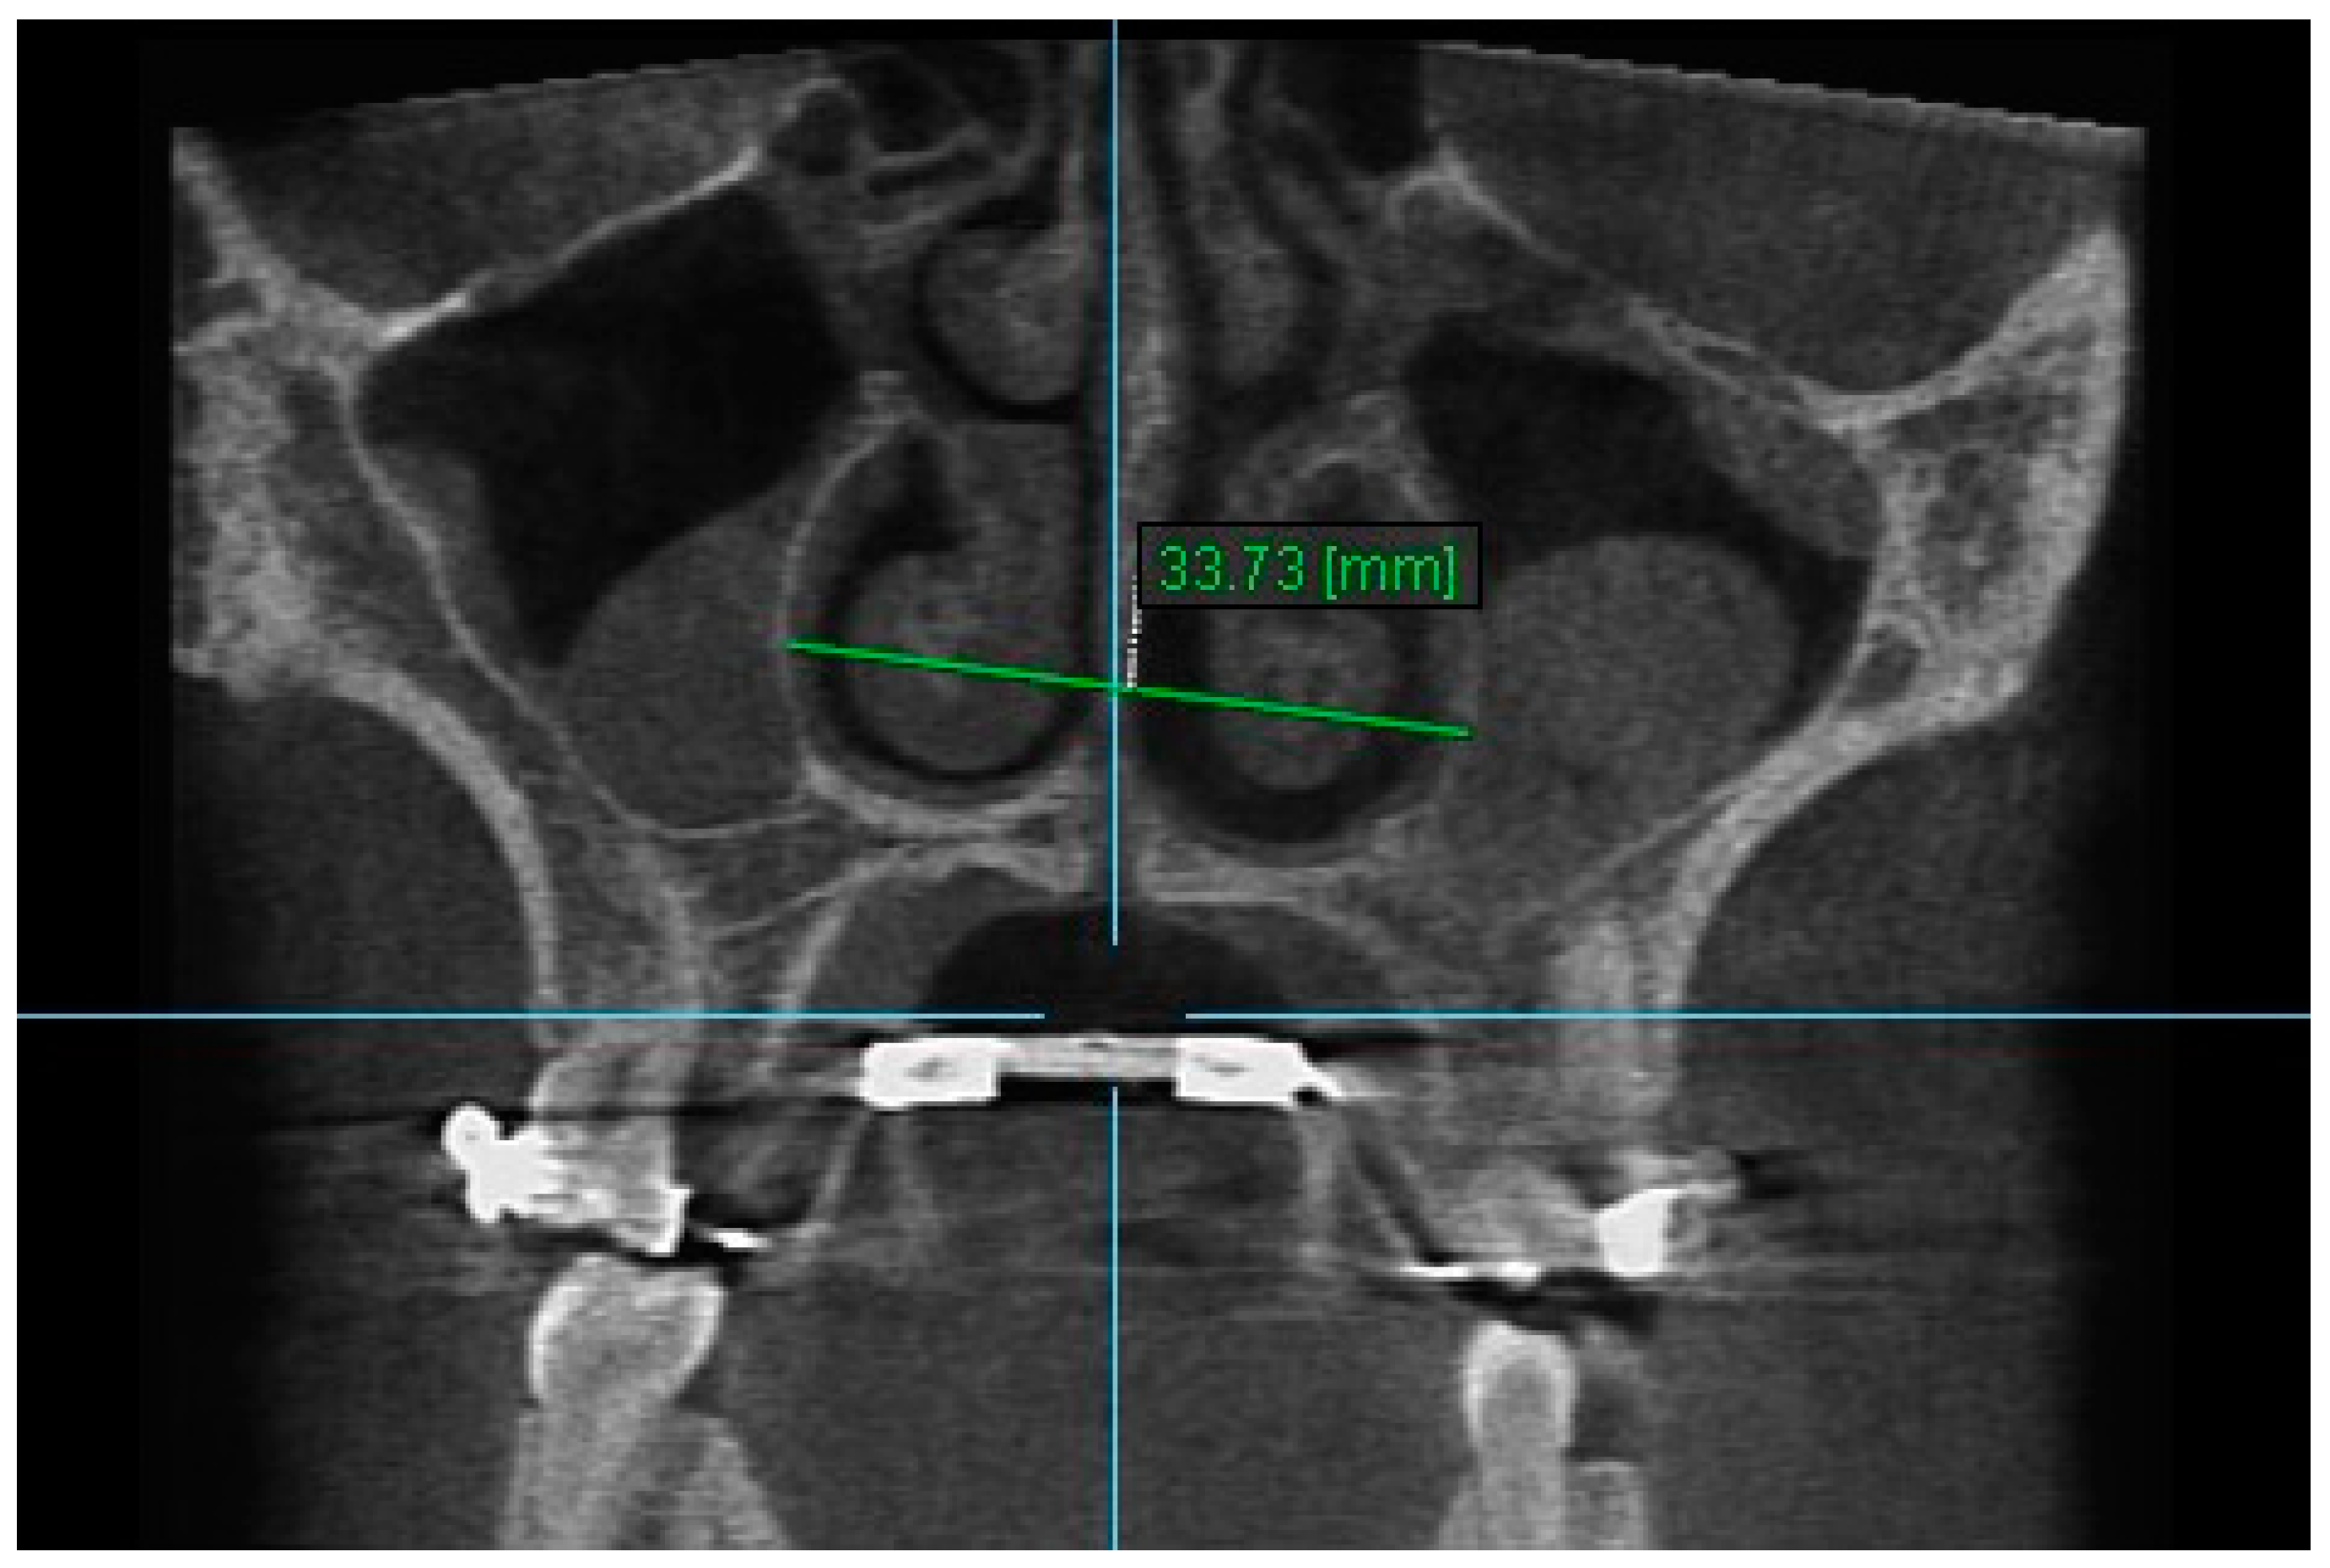

| Nasal Width 1 | T1 | 30.36 ± 2.76 | 30.44 ± 2.69 | 0.998 (0.992–0.999) |

| T2 | 32.46± 2.69 | 32.47 ± 2.57 | 0.997 (0.989–0.999) | |

| T3 | 31.71 ± 2.76 | 31.72 ± 2.77 | 0.998 (0.993–0.999) | |

| Nasal Width 1 | 28.83 | 30.97 | 30.14 | 2.13 | *** | 1.30 | *** | −0.83 | ** |